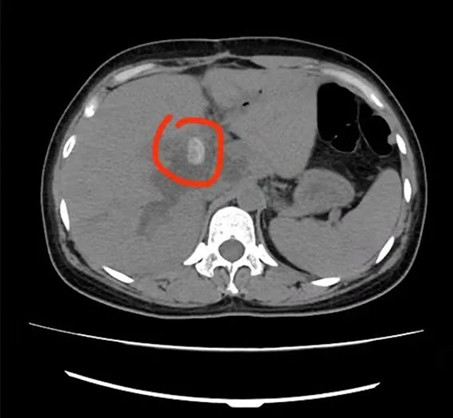

5分鐘后,楊林副主任便趕到急診科,這時腹部CT結果已經(jīng)出來:肝內(nèi)外膽管多發(fā)結石,肝內(nèi)外膽管擴張;膽囊切除后;肝門下緣胃大彎旁囊性病變伴高密度影。

綜合患者病情,楊林副主任認為其是典型的感染性休克;化膿性膽管炎;肝內(nèi)外膽管結石,如不立刻進行手術,會出現(xiàn)嚴重的并發(fā)癥甚至危及生命。

術前

術后

據(jù)悉,術中共取出19顆“石子”?;颊哌M入重癥醫(yī)學科(ICU)觀察,隨后病情穩(wěn)定后轉(zhuǎn)入普外科病房繼續(xù)進行治療,目前患者病情穩(wěn)定,不日即可康復出院。